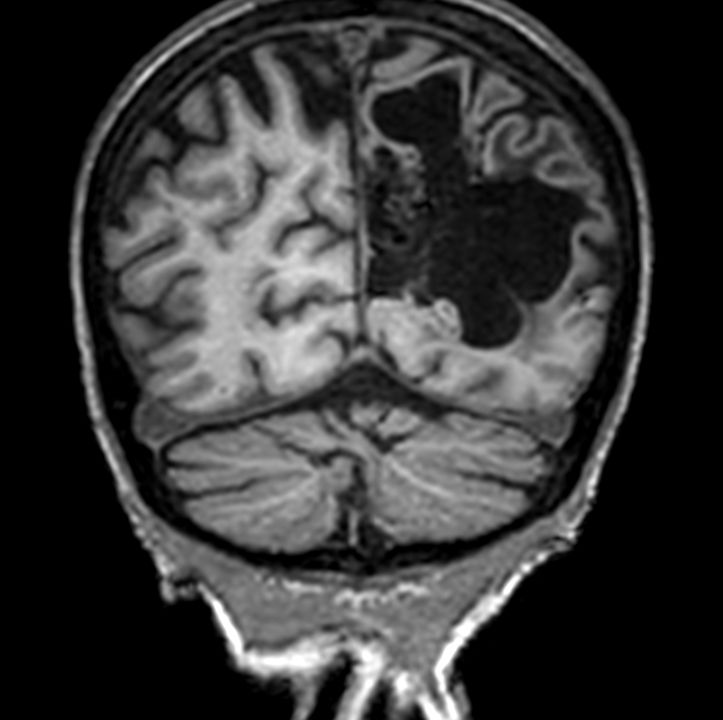

3D VIEW - T2w FLAIR (coronal reformat)

Coronal T2w TSE